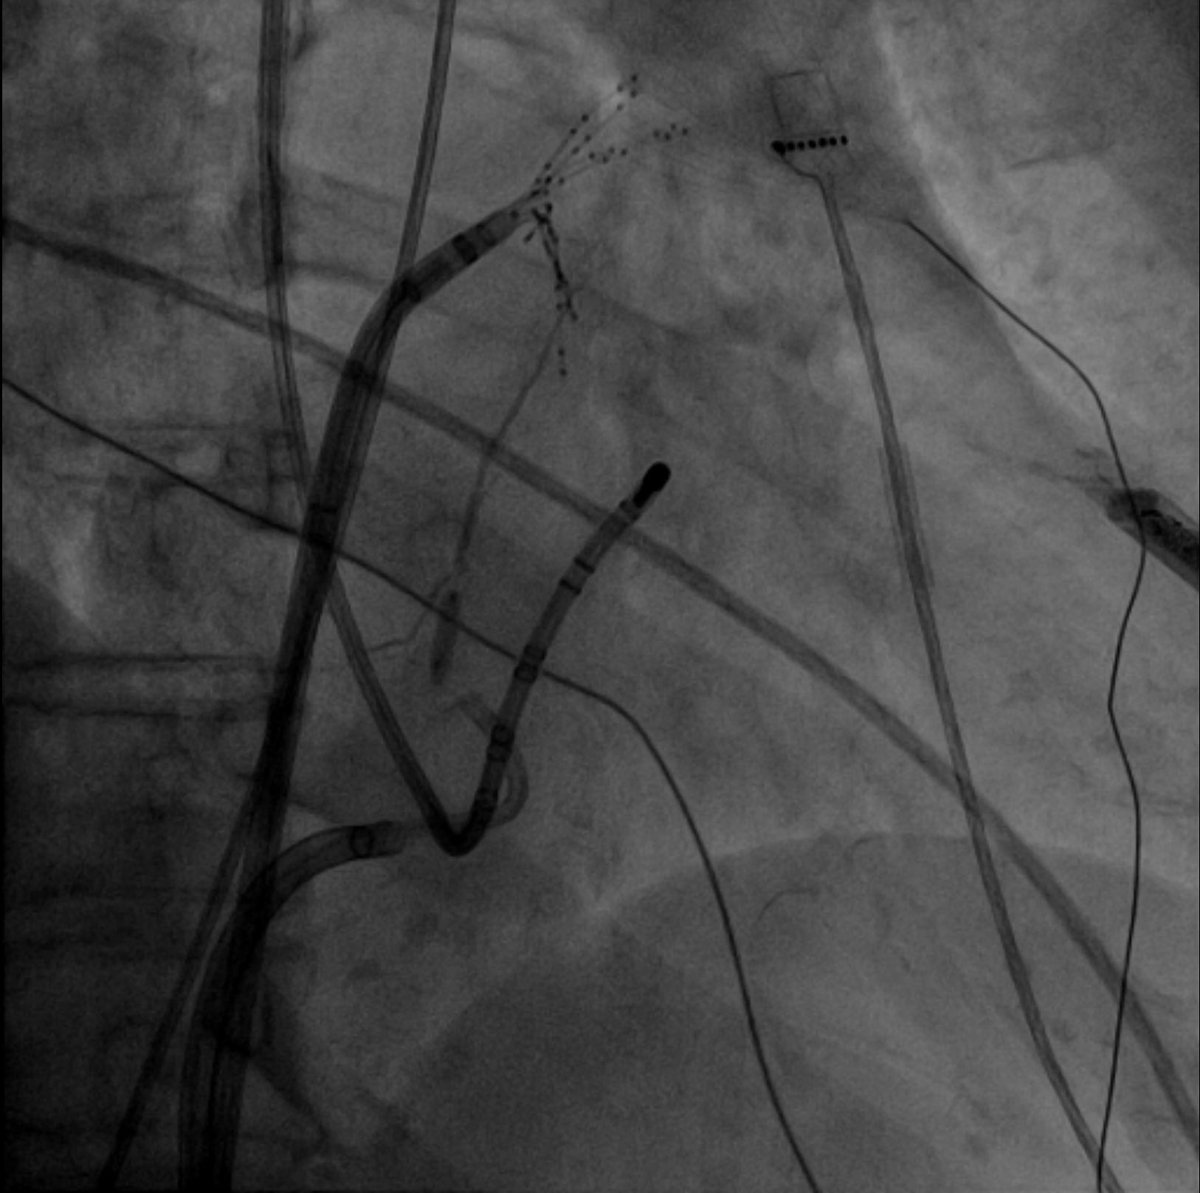

#Epeeps What’s more satisfying for an

#EP than a successful #VT ablation?

73yo M pt.

💥 VT 180 bpm

🛑 previous #MI with anterior and septal scar

Map with #Optrell, beatiful isthmus #EGMs!

🎯 SR after 7 secs RF 🔥